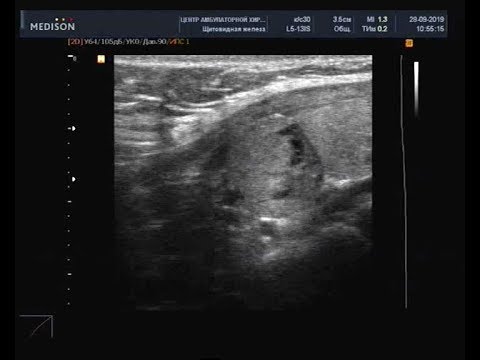

Узи tirads 3

Узи tirads 3 100 фотографий